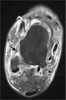

Sinus tarsi syndrome